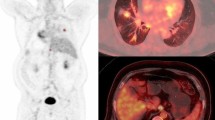

Figures 3 and 4 show typical examples of FDG-PET scans in a pathological responder and a non-responder, respectively.

CT and FDG-PET images of a 73-year-old male pathological non-responder (residual macroscopic disease) with adenocarcinoma in the left lower lobe. CT image before therapy shows a mass shadow in the left lower lobe (a). Both early (b) and delayed (c) FDG-PET coronal images before therapy show intense accumulation in the primary tumour. SUVs for early and delayed images were 6.90 and 9.24, respectively. After chemoradiotherapy, the intense accumulation in the primary tumour was slightly decreased on both early (d) and delayed (e) FDG-PET coronal images. SUVs for early and delayed images were 4.91 and 5.36, respectively. The percent change values on early and delayed images were 28.8 and 42.0, respectively. Abnormal accumulation in ipsilateral mediastinal (f early axial image, g delayed axial image) and hilar (h early axial image, i delayed axial image) lymph nodes was seen after chemoradiotherapy. Nodal stage based on early (f, h) and delayed (g, i) FDG-PET images after chemoradiotherapy was N2, but the pathological nodal stage was N1